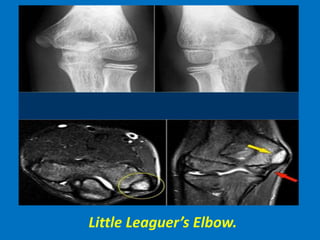

Little Leaguer’s Elbow.

The medial epicondyle of the affected arm is

somewhat more osteopenic. In these cases

we usually ask for a comparison view,

because it can be very subtle.

The diagnosis is a Little leaguer's elbow

which results from chronic stress injury.

The lucency on the radiograph, which looks

like a widened physis, is due to cartilage

ingrowth in the metaphysis.